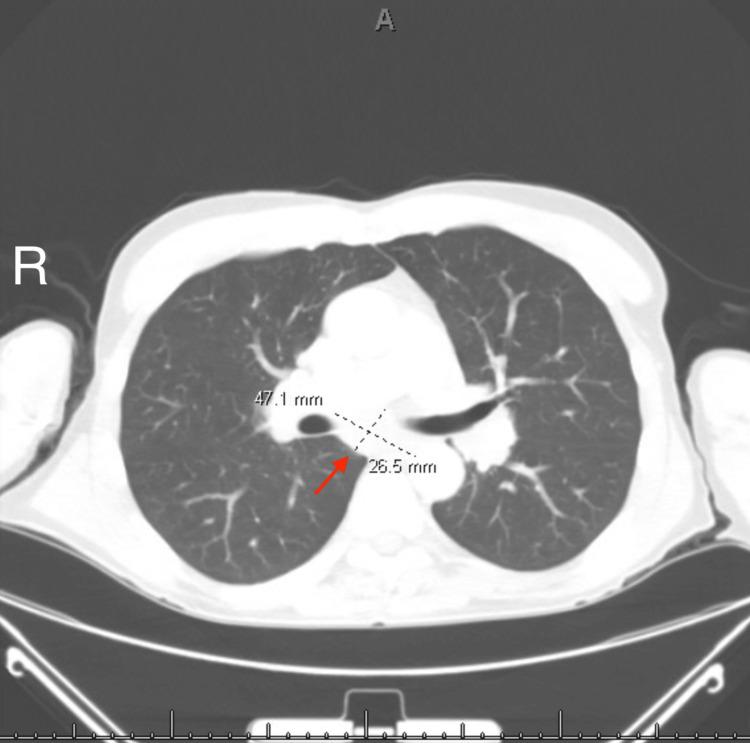

Sarcoidosis is a multisystem granulomatous disorder with an unknown etiology that typically involves the lungs, skin, and lymph nodes, with neurological involvement being relatively rare. We discuss a case of neurosarcoidosis in a 64-year-old man who initially presented with unexplained cognitive impairment, insomnia, hyponatremia, paresthesias, and weight loss and later developed uveitis, diplopia, and dysphagia. Ultimately, findings of hilar and mediastinal lymphadenopathy on chest computed tomography (CT) resulted in bronchoscopy, which led to the diagnosis. This case highlights a rare presentation of sarcoidosis with an unusual constellation of symptoms. We discuss the difficulty involved in diagnosing this disorder as well as its highly variable course.

结节病是一种病因不明的多系统肉芽肿性疾病,通常累及肺部、皮肤和淋巴结,神经系统受累相对少见。我们讨论一例64岁男性神经结节病病例,该患者最初表现为不明原因的认知障碍、失眠、低钠血症、感觉异常和体重减轻,后来出现葡萄膜炎、复视和吞咽困难。最终,胸部计算机断层扫描(CT)显示肺门和纵隔淋巴结肿大,进而进行了支气管镜检查,从而确诊。该病例突出了结节病一种罕见的表现形式,伴有一系列不寻常的症状。我们讨论了诊断这种疾病的困难以及其高度多变的病程。